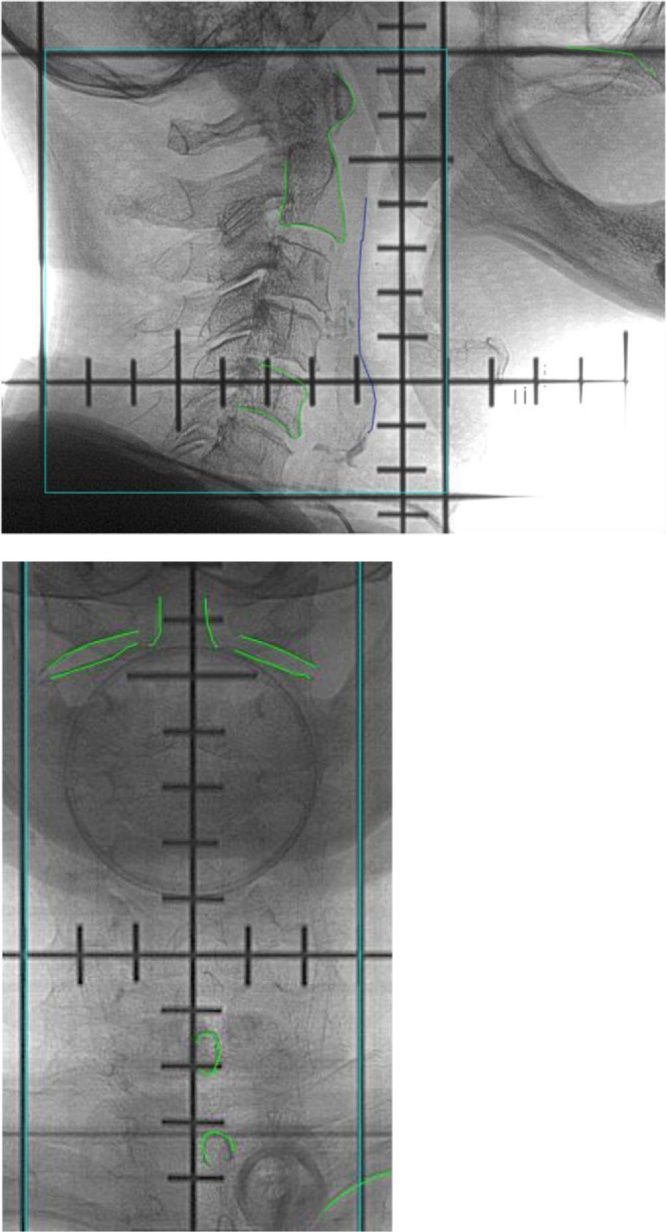

The analysis was carried out for 30 H N patients treated in our center. These were patients with nasopharyngeal and larynx cancer. For each patient a customized 5-point head, neck and shoulders thermoplastic mask (Orfit Industries, Belgium) was made. In addition, a standard, but individually chosen, head support was used. All patients underwent a planning CT scan with 2 mm slice thickness. The scanned region was the PTV plus about 5 cm cranially and caudally. The central axes (three small crosses) were marked on the mask. All the images were sent to the contouring station for target and critical structures delineation. For each patient, an IMRT or VMAT plan was prepared. For almost all patients, the integrated simultaneous boost technique was used. The isotropic margin CTV-PTV of 3–4 mm was always added. The Digitally Reconstructed Radiographs (DRR) are prepared for vertical and lateral position of the gantry. On each DRR, before start of the treatment, the contours of stable anatomical structures were drawn. The anatomical structures used for matching are shown in Fig. 1. During the treatment, the setup position of the patient was accomplished by aligning the lasers with the points marked on the masks. If needed, the position of the isocenter was achieved by treatment couch shifts.

Fig. 1.

Digitally Reconstructed Radiographs, AP and lateral, with edges of anatomical structures used for matching. Edges in green (For interpretation of the references to colour in this figure legend, the reader is referred to the web version of this article).